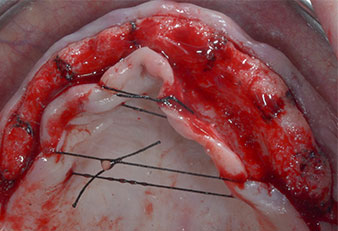

Фиг. 1 Предварителен изглед на максиларния гребен с позиции на имплантите, маркирани с помощта на хирургичен водач. Поради ниския алвеоларен гребен са планирани супер къси импланти в дисталните зони.

Позиции на имплантите

Фиг. 2 След инцизия в средата на алвеоларния гребен и препариране на мукопериостални ламба, позициите на имплантите са трансферирани в костта.